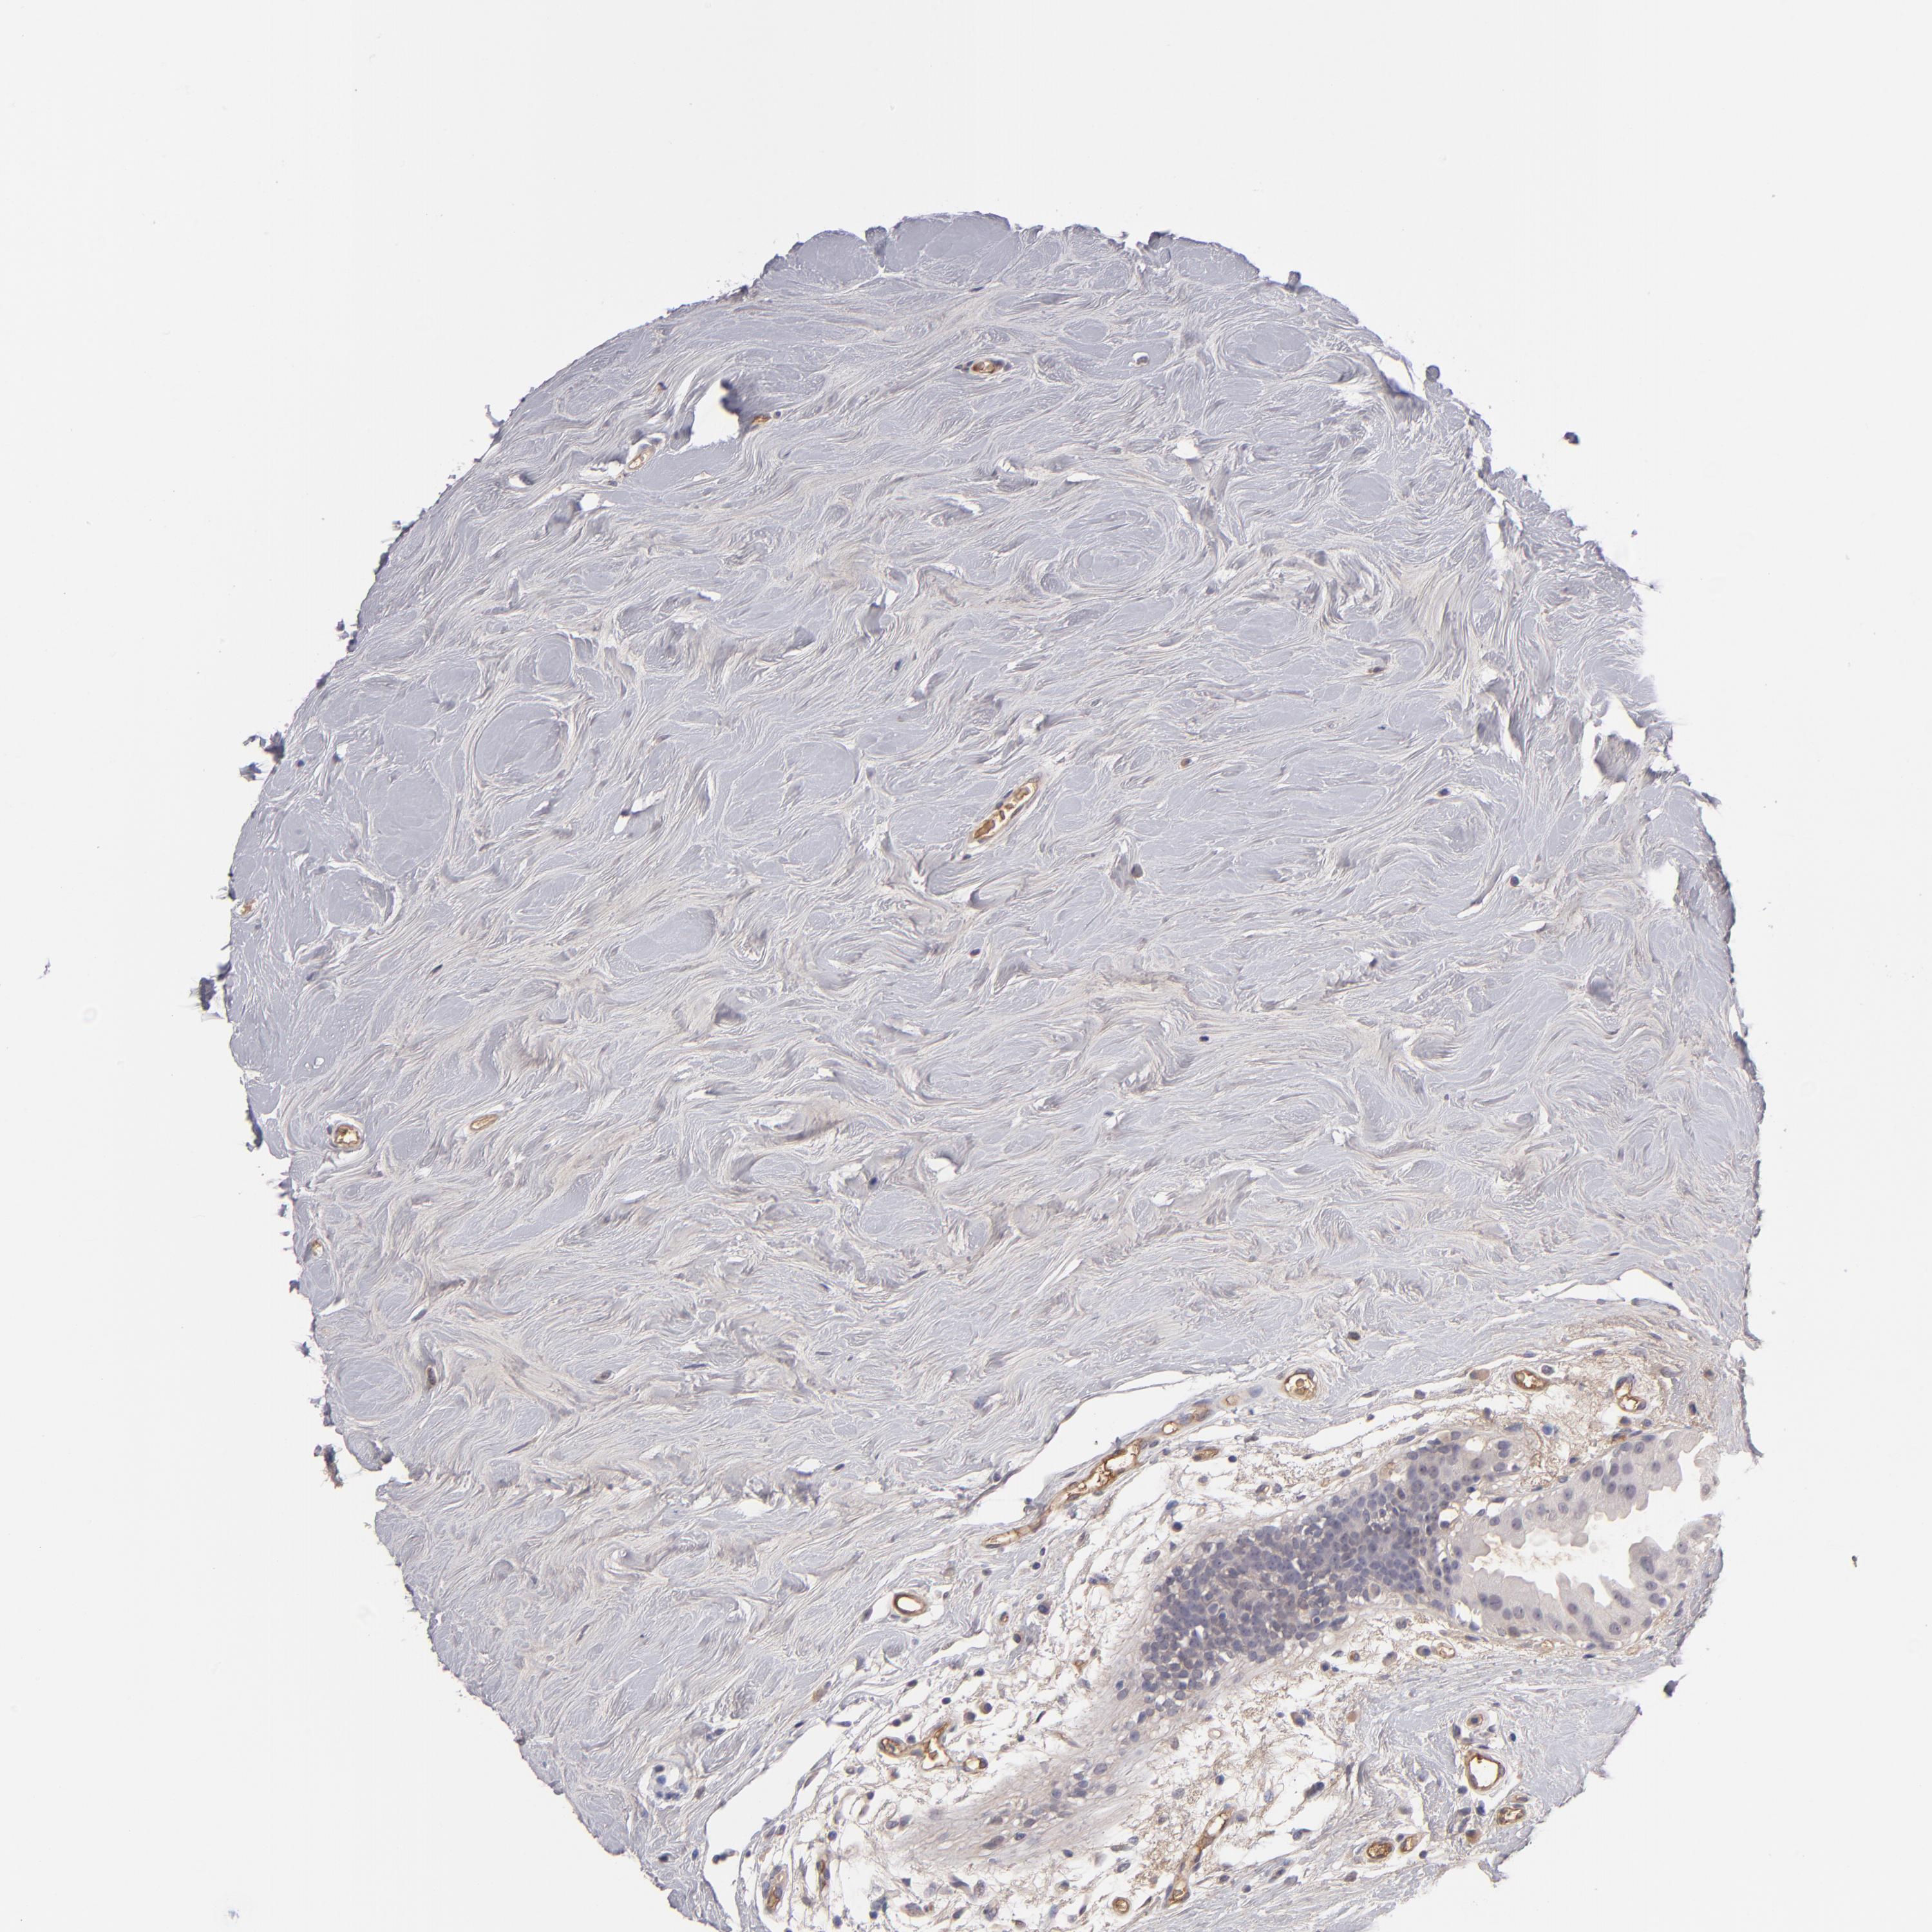

BRCA TCGA BRCA VALIDATION PROTEIN EXPRESSION

ANTIBODIES

AND

VALIDATION